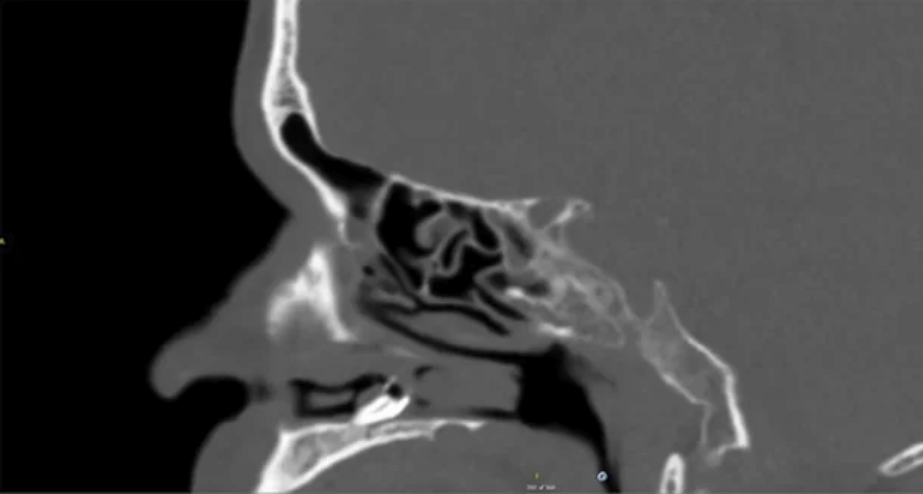

Bildkälla: BMJ Case Reports)

När mannen besökte Århus Universitetssjukhus fick han träffa läkaren Jesper Højager Fabech Bille och efter en första undersökning tog han beslutet att göra en datortomografi, vilket är en undersökning som används för att avbilda patienten i tre dimensioner.

Då hittade läkaren problemet med mannens näsa.

Långt upp i den vänstra näsborren växte en tand.

Efter att ha sett röntgenbilderna kunde läkaren konstatera att mannen hade en växande tand inne i näsan.

– På bilden kan man se rotkanalen. Tanden satt längre upp än vad ett finger kan ta sig upp i näsan, säger Jesper Højager Fabech Bille till tidningen.

Tanden som växte i mannens näsa var lika stor som toppen på en kulspetspenna och läkaren tror att den måste ha suttit där sedan mannen föddes, skriver Jesper Højager Fabech Bille och två av hans kollegor i rapporten som publicerats i den vetenskapliga tidskriften BMJ Case Reports.